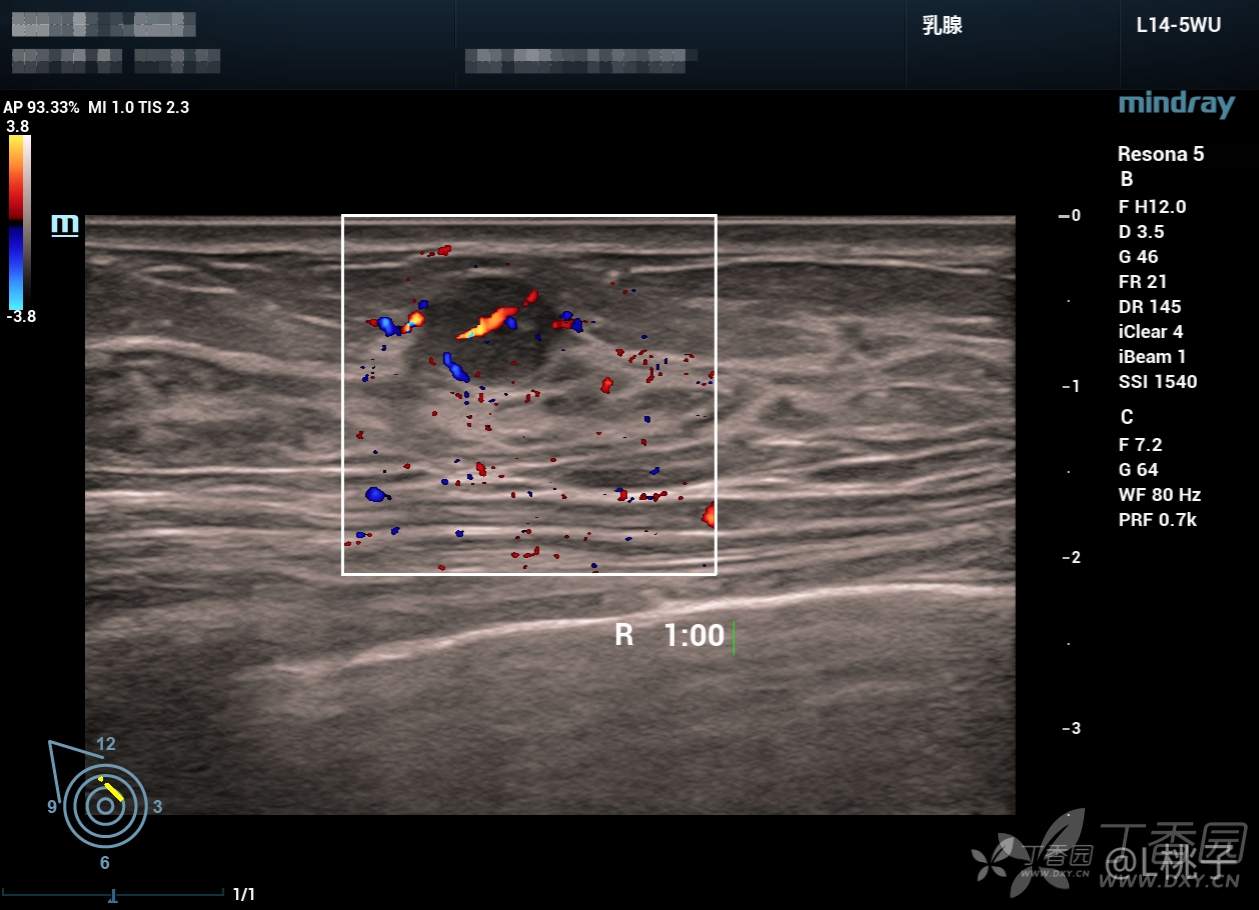

发部分乳腺结节的病例

大家考虑一下分级

病例1: